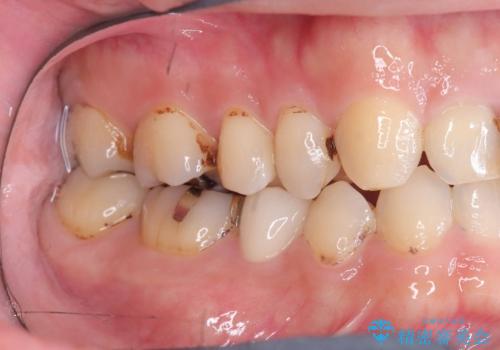

- CRの下が虫歯になっており歯が欠けている状態でした。古いCRと虫歯を除去しセラッミクインレーで治療しました。

CRが劣化し虫歯になり欠けている状態でした。歯を長持ちさせるために(再治療を減らす)セラッミクインレーで治療を行いました。

右上4のCRも劣化していてかつ形態も良くないので治療の必要性はご説明させていただきました。